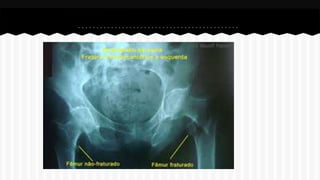

RESPONDA O NOME DO OSSO EM QUE

SE ENCONTRA A (S) FRATURA (A).